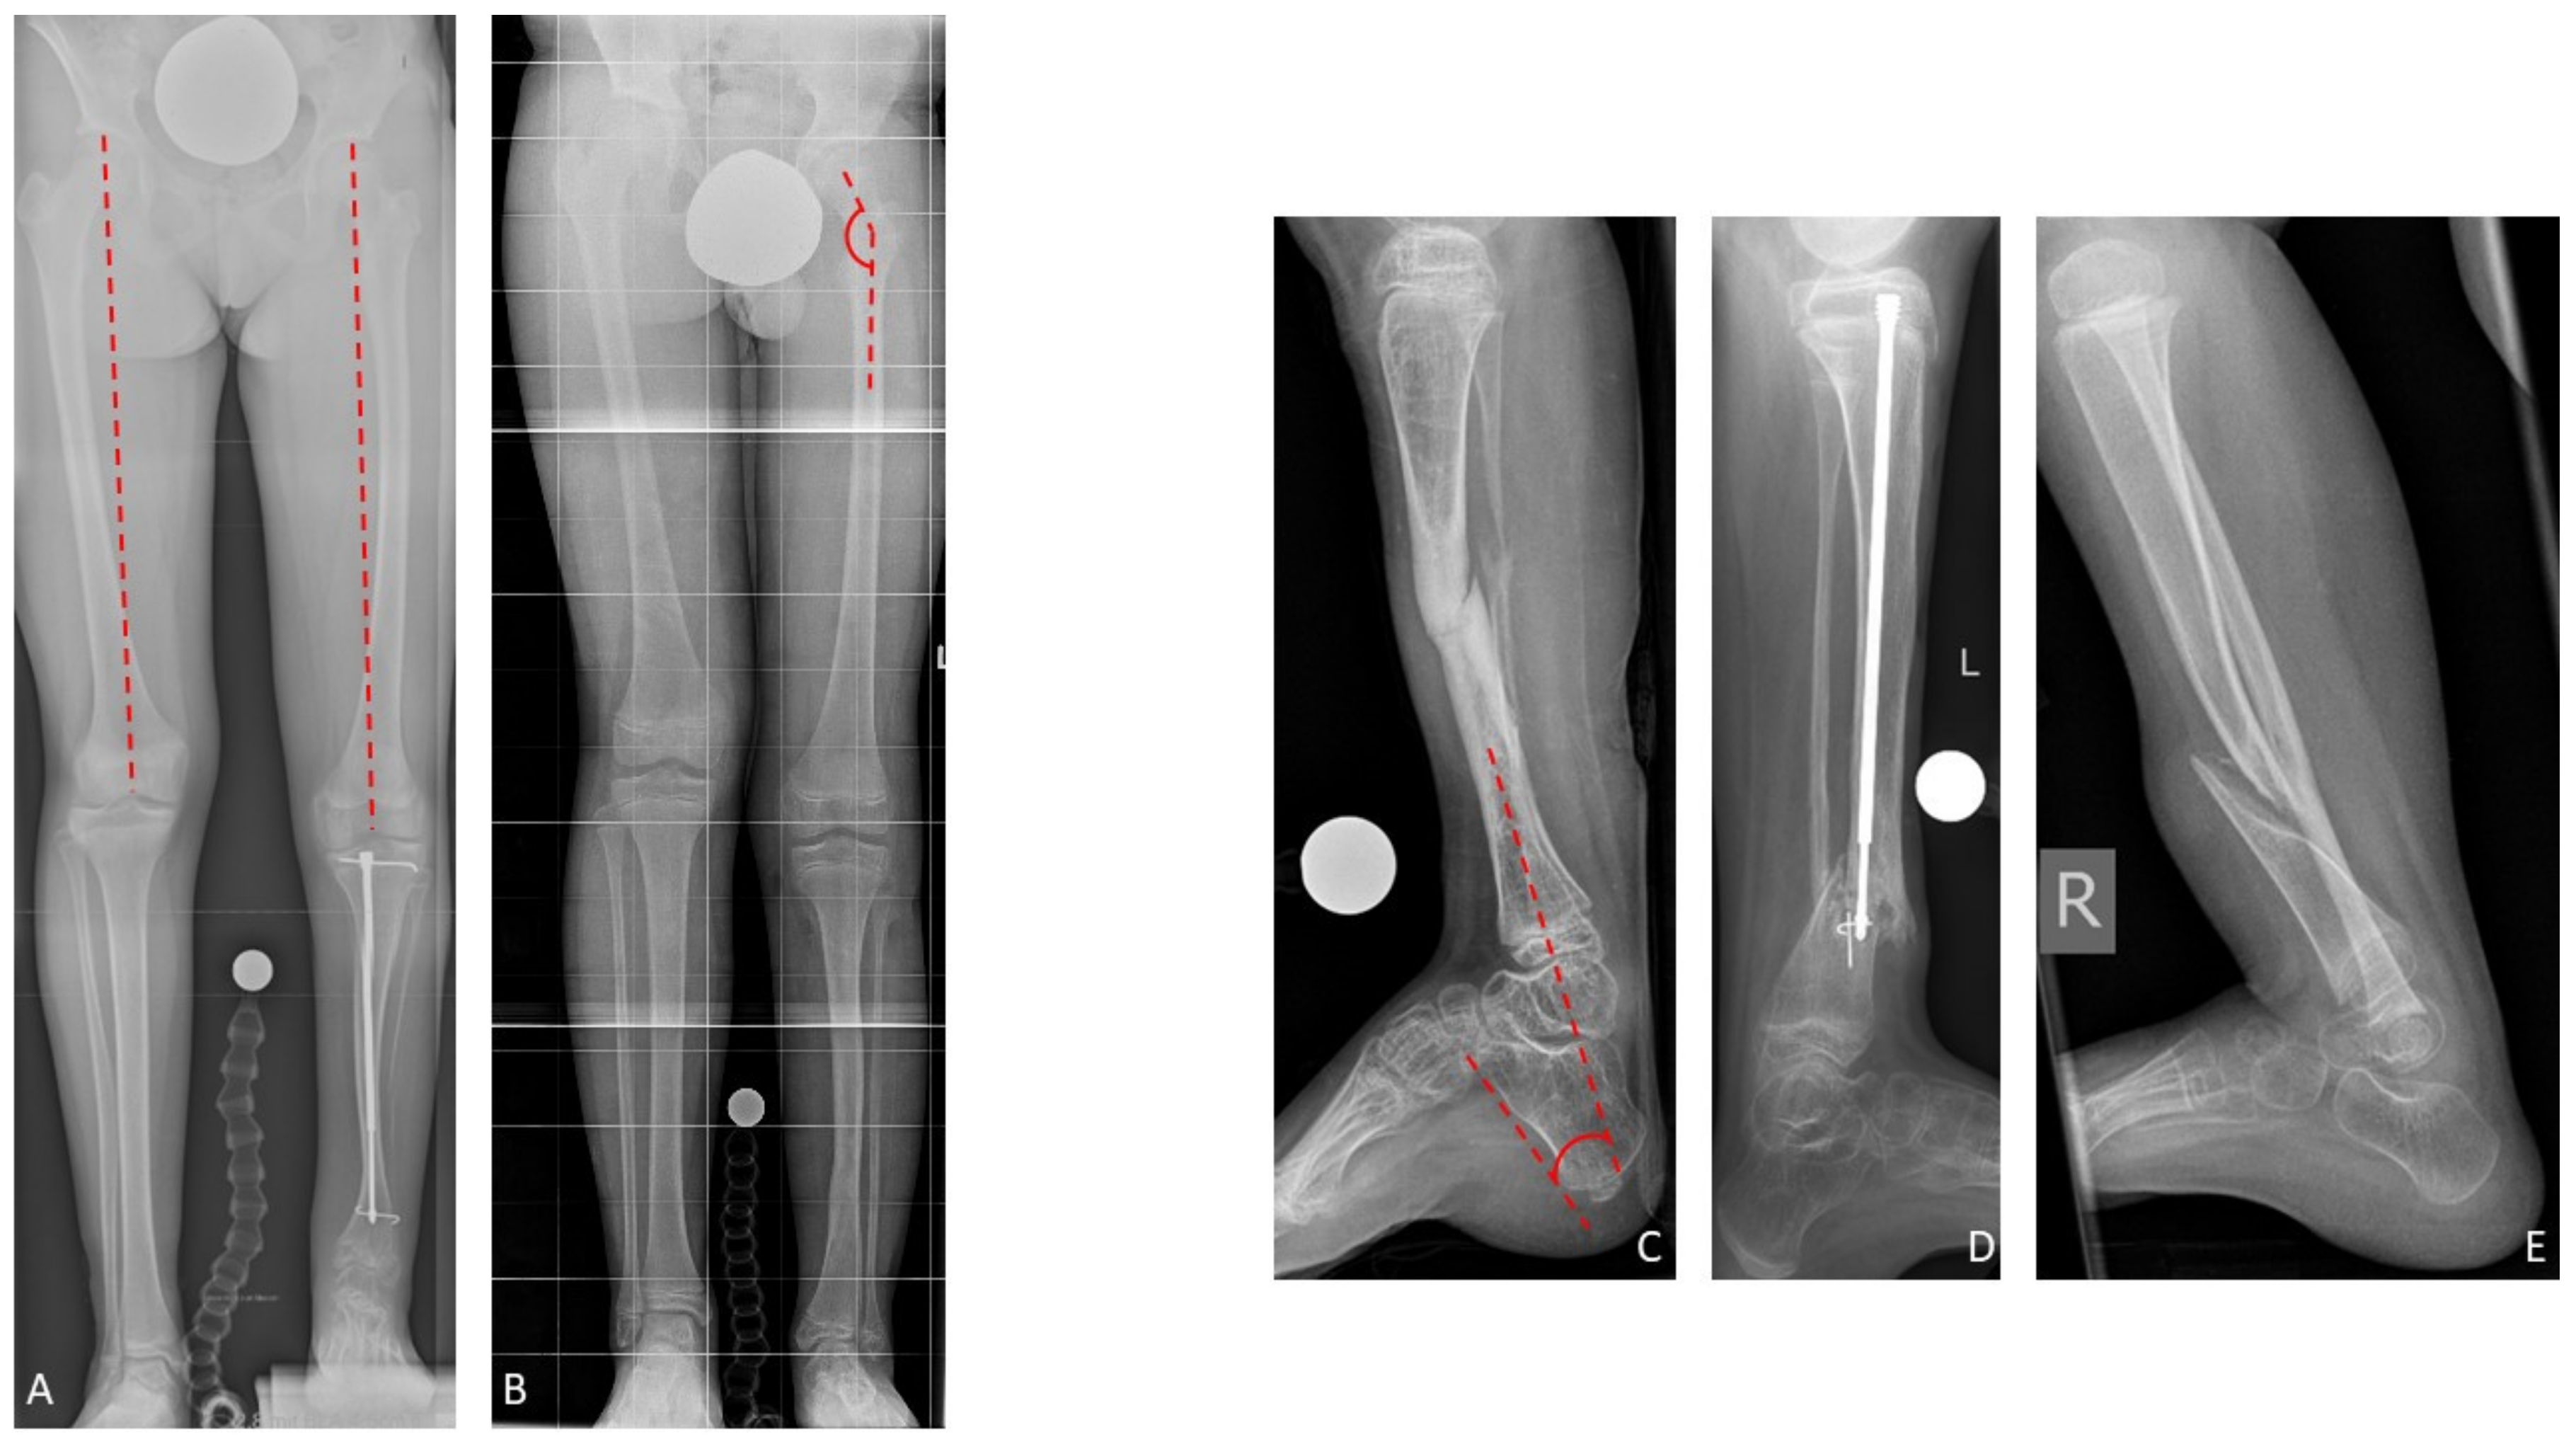

Nine of 19 patients (47%) of whom radiographs of both femora were available presented femoral overgrowth with a femoral segment which was ≥10.0 mm longer than the contralateral femur. All of them additionally showed coxa valga. In total, 17 of 21 patients (81%) with radiographs of the ipsilateral femur presented coxa valga. The mean neck-shaft angle in the study cohort was 148.1 (130–164) degrees on the leg affected by CPT, and 132.9 (119–149) on the contralateral side. Pes calcaneus was present in 16 of 24 patients (67%) in whom the tibiocalcaneal angle could be evaluated. Pes calcaneus was defined by a tibiocalcaneal angle below 60 degrees. Overall, the mean tibiocalcaneal angle measured 55.8 (23–78) degrees on the leg affected by CPT (

Figure 5). The contralateral tibiocalcaneal angle could not be evaluated as lateral radiographs of the contralateral leg were not available.